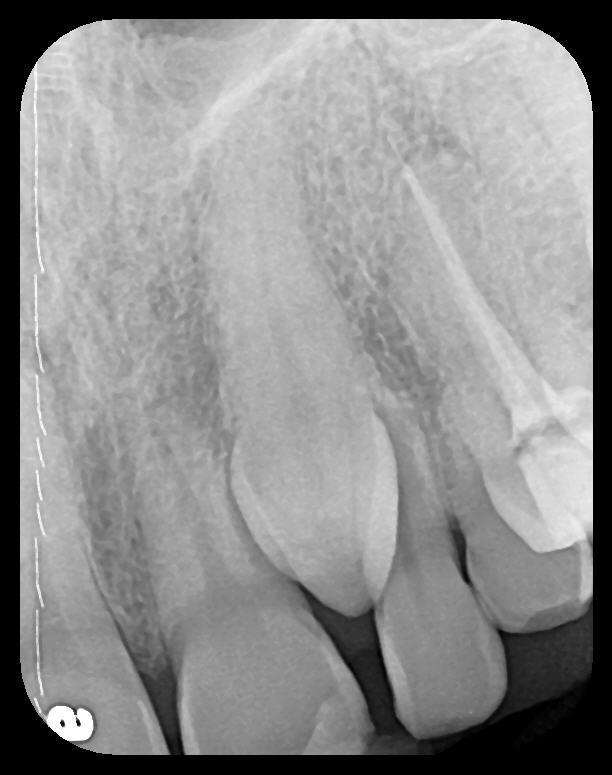

Fig 9. Endodontic obturation overfill visible on PA radiograph, which is

escaping the apex of tooth No. 14 and extruding into the left maxillary

sinus. A pathologic sinus congestion, in the form of a slight radiopacity

within the sinus, is noted in response to the foreign material.

Figure 9